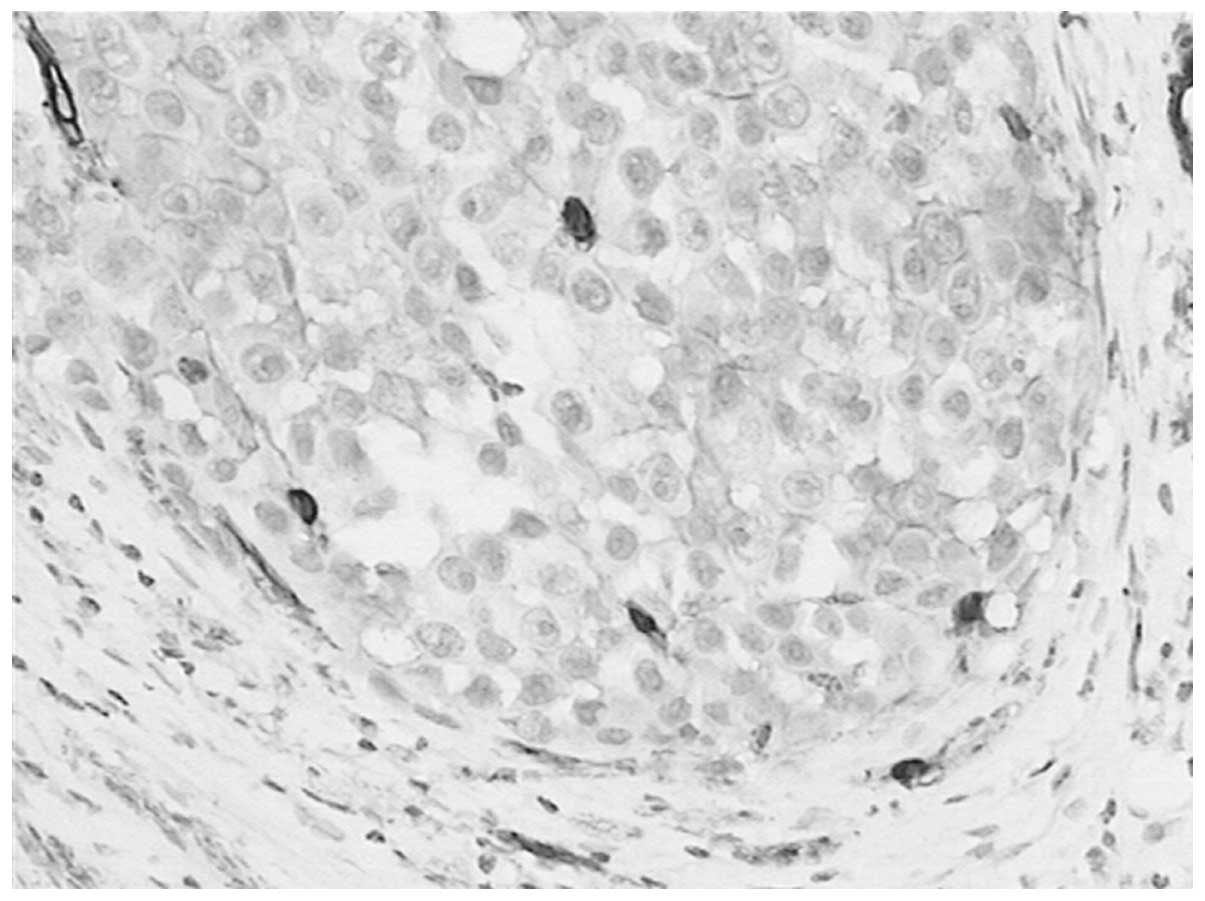

Correlation of CD146 expression and clinicopathological characteristics in esophageal squamous cell carcinoma

CD146, a cell adhesion molecule, is found in normal and tumor tissues. The level of its expression has been found to directly correlate with tumor progression and metastatic potential. The objective of this study was to investigate the expression of CD146 in esophageal squamous cell carcinoma (ESCC) and its correlation with clinicopathological parameters. Tumor specimens were collected from 63 patients with ESCC who underwent complete resection. We analyzed the CD146 expression levels in ESCC by immunohistochemistry. The expression of CD146 was detected and it was observed to correlate with clinicopathological parameters. Sixty‑three cases of normal squamous mucosa were included for comparison. CD146 expression was identified in 46.0% (29/63) of the ESCC samples, and no positive (weak to moderate or moderate to strong) expression was found in the normal squamous epithelium samples (χ2=27.248; P<0.0001). CD146 expression was associated with lymph node metastasis (χ2=5.117; P=0.024) and advanced clinical stage (χ2=4.661; P=0.031). CD146 expression was one of the significant predictors of survival (hazard ratio, 2.838; 95% confidence interval 1.102‑7.305). The overexpression of the CD146 gene was one of the important phenotypes and characteristics in ESCC carcinomatous change. We found that CD146 expression was associated with lymph node metastasis and advanced clinical stage, and was an indicator of poor prognosis in ESCC patients. CD146 may prove to be an important tumor marker for the individualized treatment for ESCC.

View Figures

Figure 1

Figure 2

Figure 3

Figure 4

Figure 5

Figure 6

Figure 7